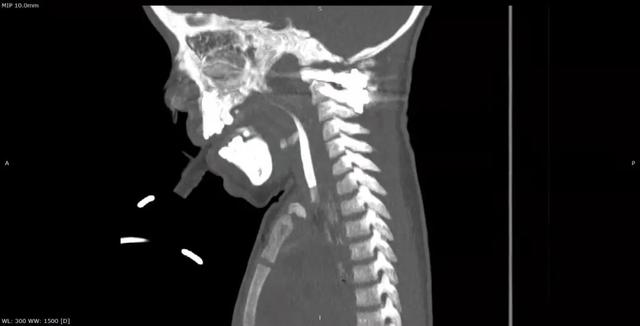

al-align:top;”> 孩子,望你早日康复! 这是一个关于 2岁宝贝的故事 为何这个幼儿平地摔倒,外表毫无受伤痕迹,却出现全身瘫痪,甚至呼吸功能衰竭? …… 为何凌晨时分,重医一院急诊科传来了救护车急促的汽笛声? …… 病史 患儿女,2岁零11个月; 于家中玩耍时平地跌倒致短暂意识丧失,苏醒后四肢瘫痪,自主呼吸微弱,病情危急! 为什么? 影像 患儿在当地医院作了急诊CT检查,发现…… CT显示:寰枢关节不稳 MRI:患儿呼吸不好,病情已不允许作了 分析 1. 尽管没有MRI检查,但根据CT显示的寰枢椎不稳,结合患儿四肢瘫痪,自主呼吸微弱的症状,颈延髓损伤明确; 2. 临床诊断:1)寰枢椎脱位 2)颈延髓损伤 怎么办? 方案 刻不容缓,做急诊手术准备! 寰枢关节不稳必须立即解决,否则有延髓再损伤的风险! 急诊手术:“寰枢椎复位+颈1-2融合内固定术+后路寰枕减压” 难点 患儿年龄小且发育较差,身高较同龄幼儿少10cm,体重仅仅11kg,上颈椎手术本就属脊柱高危手术之一,而幼儿的上颈椎骨质细小,在幼儿的上颈椎进行内固定手术,更是难上加难; 经验 重庆医科大学附属第一医院虽然是一所主要面向成人的综合性医院,但本院神经外科脊柱亚专业组,在幼儿脊柱手术方面具有丰富经验,尤其是对幼儿上颈椎损伤、颅底凹陷、先天性颅颈畸形、寰枢椎脱位等疾病,手术技术娴熟,成功完成过从2岁至13岁不同年龄幼儿的上颈椎手术。 既往病例文章分享: # 从13岁到2岁 # 一例“复杂”幼儿颅颈畸形 # 挑战幼儿 —— 3岁11月颅颈畸形手术病例分享 # 病例分享 || 幼儿复杂颅颈畸形 ……………… 本例患儿的手术在入院后2小时立即进行,并成功完成。解决了患儿寰枢椎不稳的风险,为其后续治疗的安全性提供了强有力的保障。 术后情况 术后CT示寰枢椎完美复位,寰枕区减压充分, 避免了患儿颈延髓神经功能二次损伤可能,为康复争取时间! 小宝贝术后虽然颈椎稳定了, 也减压了。 但是一时还无法脱离呼吸机, 也无法离开监护室, 无法见到自己爸爸妈妈! 不要害怕,宝贝! 重医一院神经外科脊柱亚专业组 和神经重症亚专业组的叔叔阿姨们 以及神经外科的护士小姐姐们, 会一直守护在你身边, 为你保驾护航! 宝贝加油! 相信你一定能战胜病魔,茁壮成长! 老晏说 幼儿脊柱疾病,亦在重庆医科大学附一院神经外科!